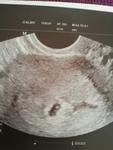

Dr těhotenství potvrdil ale jsme o tyden menší to asi tím že ms chodí po 33 dnech za 10 dní další kontrola to už snad uvidíme i 💕